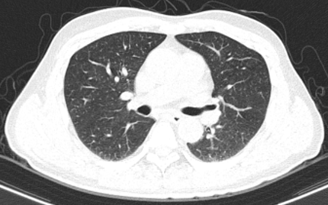

– Chụp cắt lớp vi tính ngực:

Hình 2: Hình ảnh chụp cắt lớp vi tính lồng ngực: Không thấy các tổn thương thứ phát